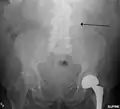

A ruptured AAA with an open arrow marking the aneurysm and the closed arrow marking the free blood in the abdomen

The faint outline of the calcified wall of an AAA as seen on plain X-ray